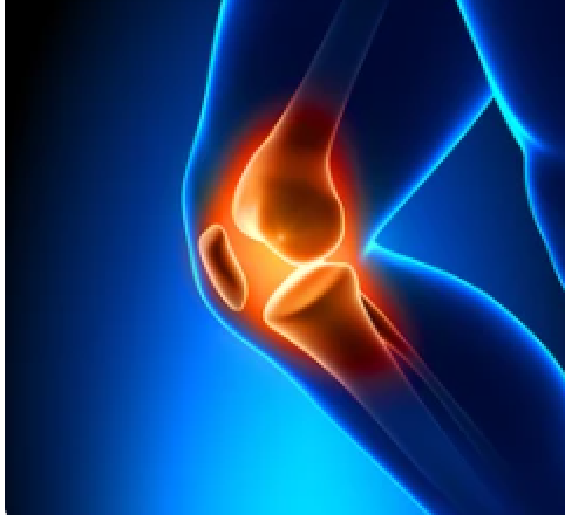

Pulsed PEMF therapy sends magnetic energy into the body. These energy waves work with your body’s natural magnetic field to improve healing. The magnetic fields help you to increase electrolytes and ions. This naturally influences electrical changes on a cellular level and influences cellular metabolism. It works with your body’s own recovery processes to help relieve chronic pain. Best of all, it’s entirely safe.

We recommend this to patients with pain or dysfunction in their: